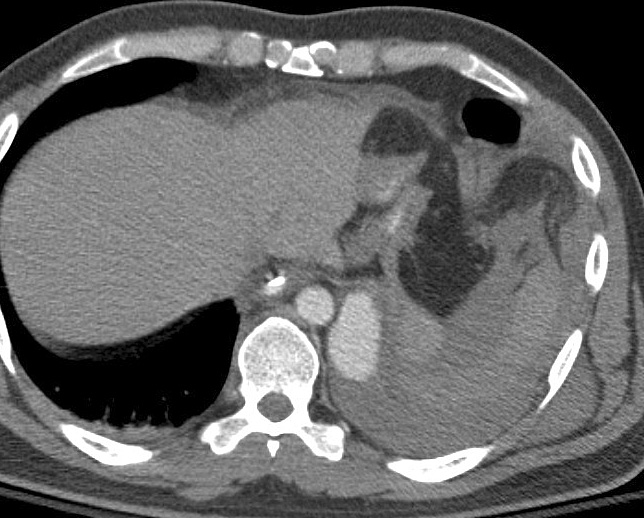

Gallery Blunt Chest Trauma Rupt HD Case 2c

Case 2c